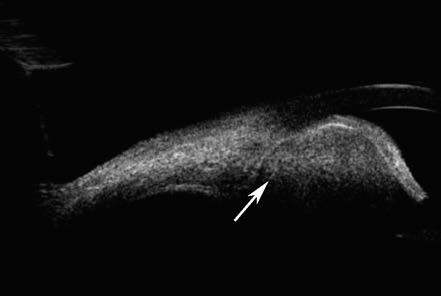

Figure 1 UBM Imaging of a non-pigmented ciliary epithelium adenoma in the left eye

The adenoma of the non-pigmented ciliary epithelium appears as a mass with inhomogeneous medium echogenicity and clear borders (white arrow).